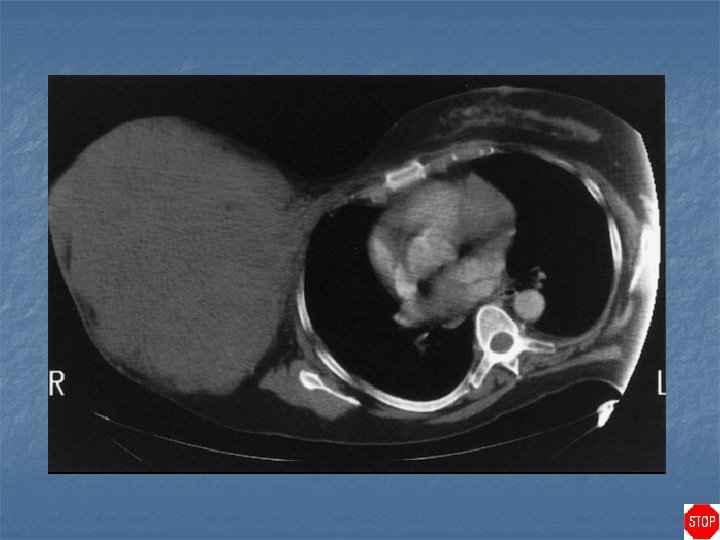

Phylloides tumor (cystosarcoma phyllodes) n Case findings: n n US: multiple solids, hyperechoic nodules with central cystic components CT: well-circumscribed tumor without obvious enhancement Age: 45 years-old Features: n n n Circumscribed round, oval or lobulated tumor, sometimes with partly indistinct borders No spiculation on mammography US: circumscribed hypoechoic lesions with varying degrees of inhomogeneity and small cystic spaces

Phylloides tumor (cystosarcoma phyllodes) n Differentiation between benign and malignant phyllodes tumors is not possible on imaging Locally invasive tumor which rarely metastasizes n DDX rapidly enlarging masses: n n n Phylloides tumor Juvenile giant fibroadenoma Abscess Hematoma

Phylloides tumor (cystosarcoma phyllodes) Predominantly circumscribed malignant phyllodes tumor

Phylloides tumor (cystosarcoma phyllodes) US: smooth margined lobulated noncompressible lesion with internal cystic spaces and varying echogenicity